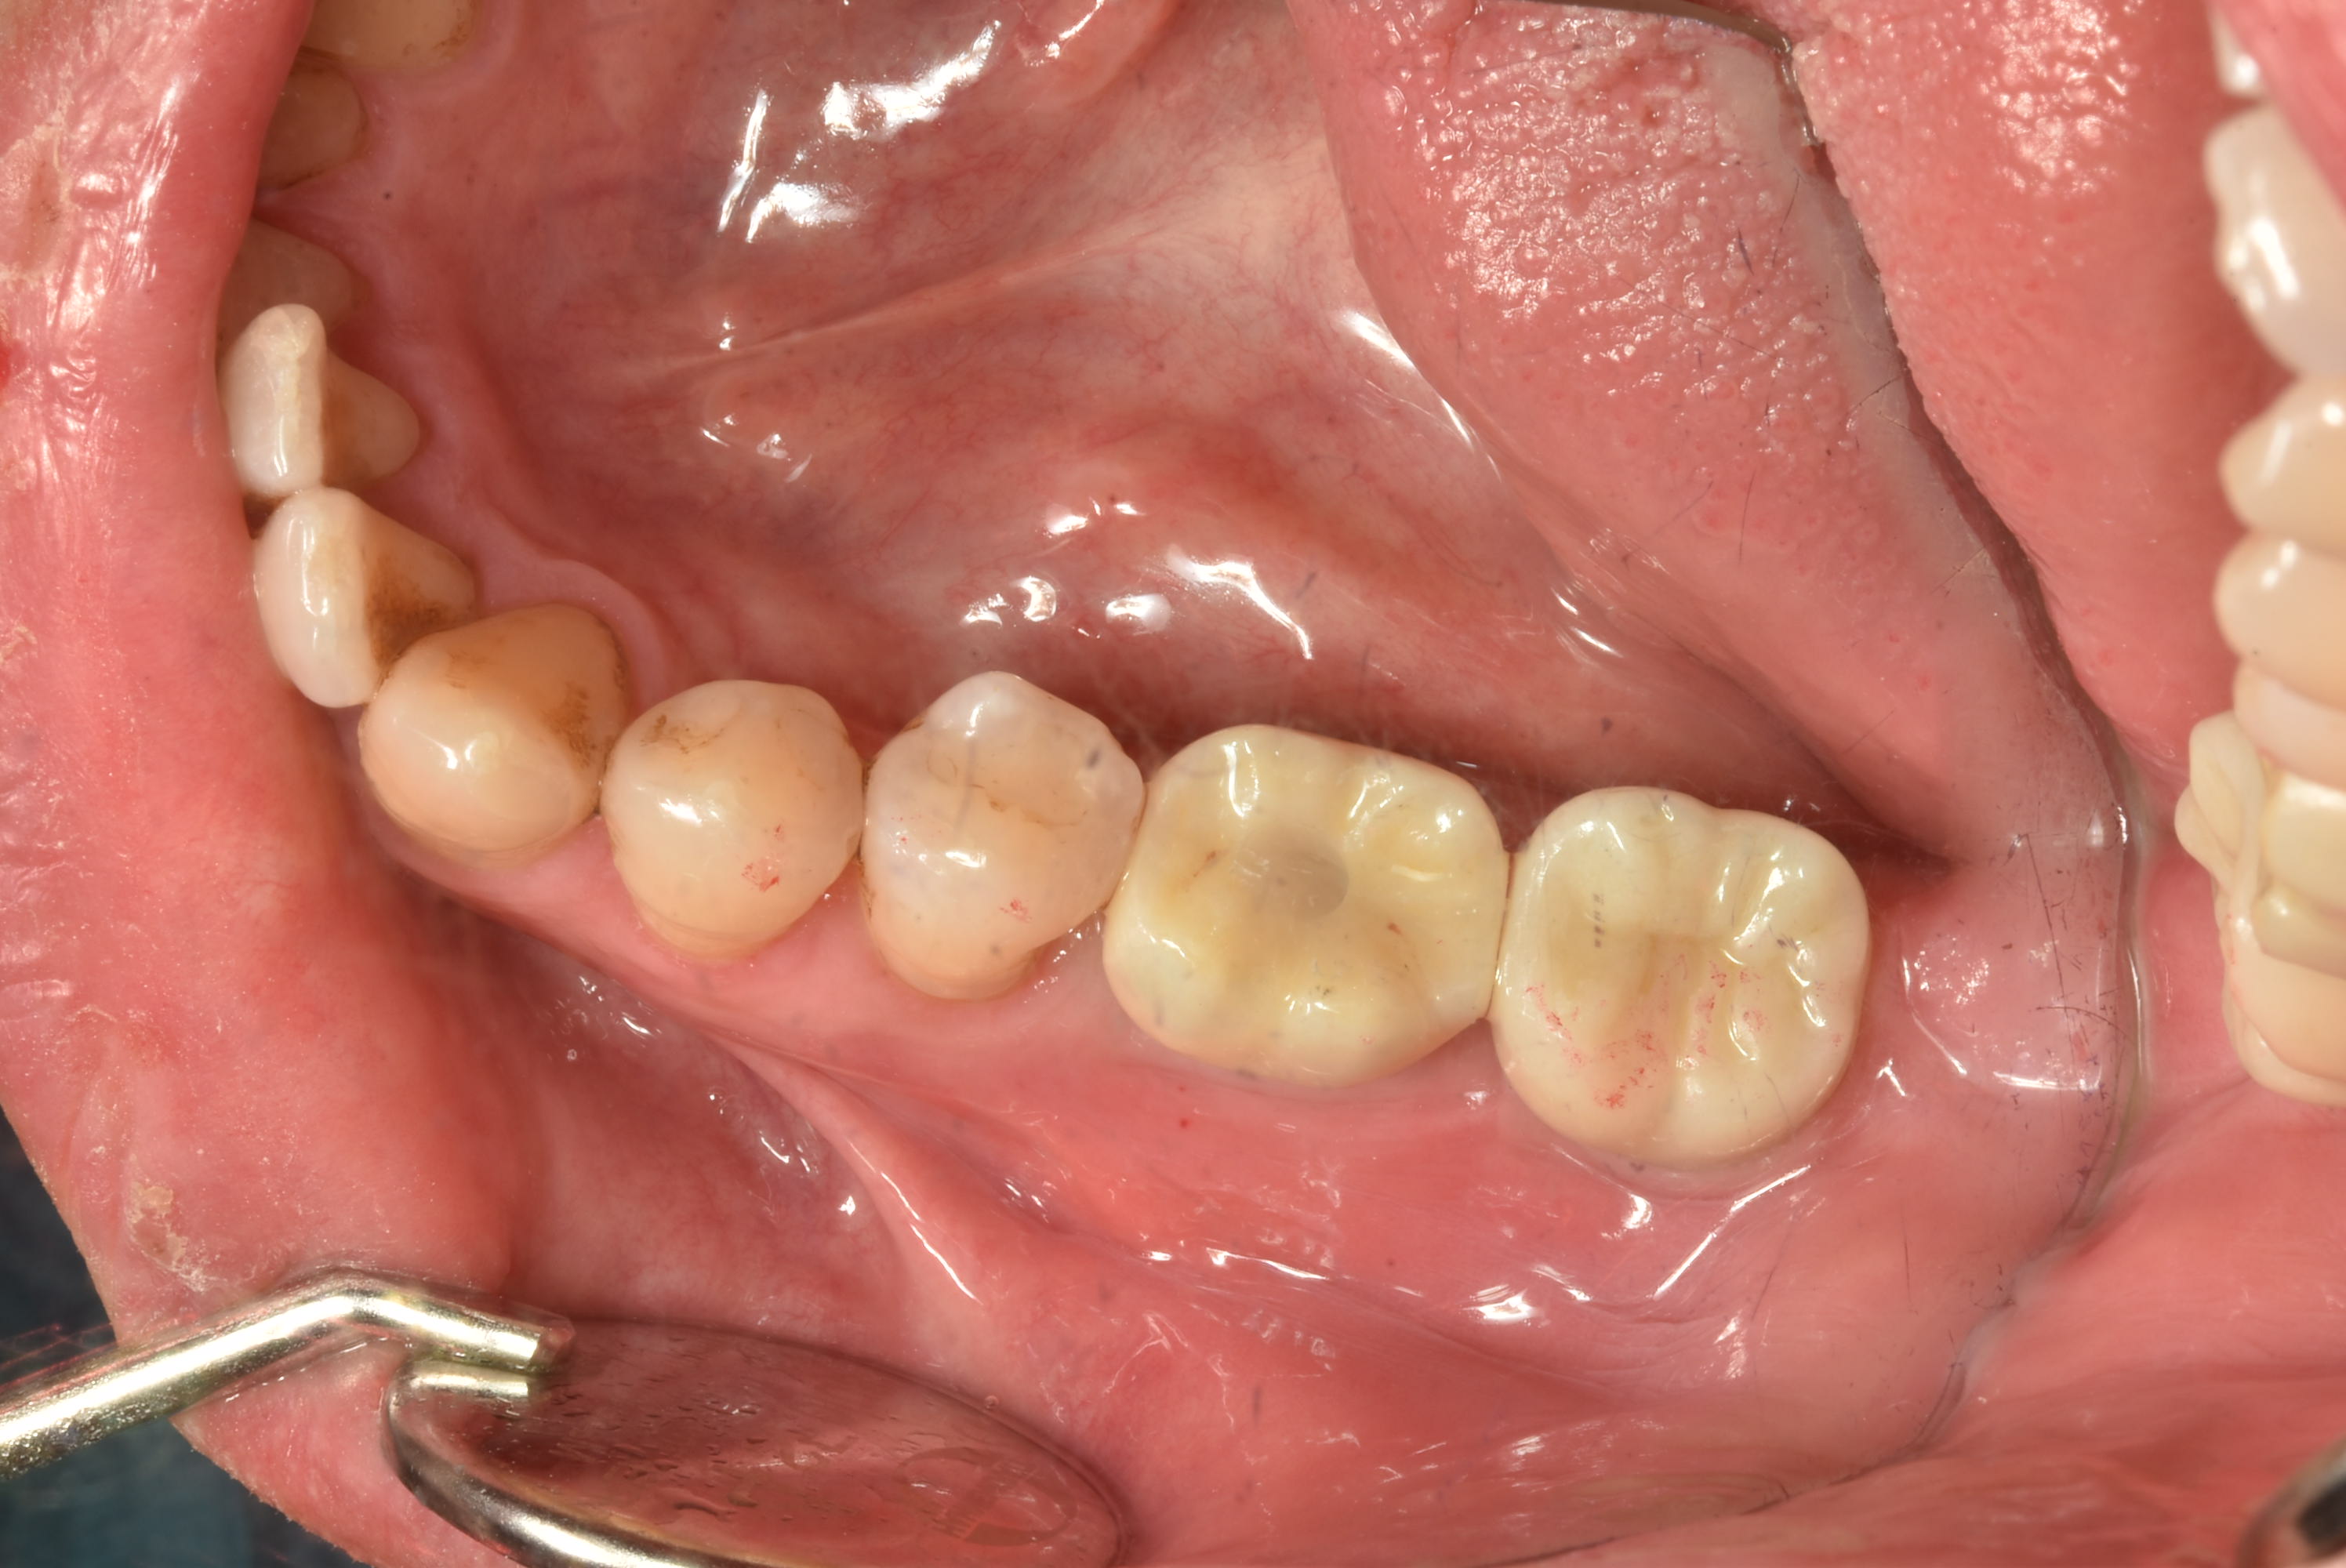

案例五

立即拔除牙根不好的牙齒

醫生透過電腦斷層評估骨頭狀況決定植入的植體所放的寬度與深度

2-3月癒合,取下癒合螺帽,透過數位口掃至技公所製作假牙

2-3個月癒合,7-10天完成假牙 ,試戴、調整咬合高度並鎖上,封填,完成